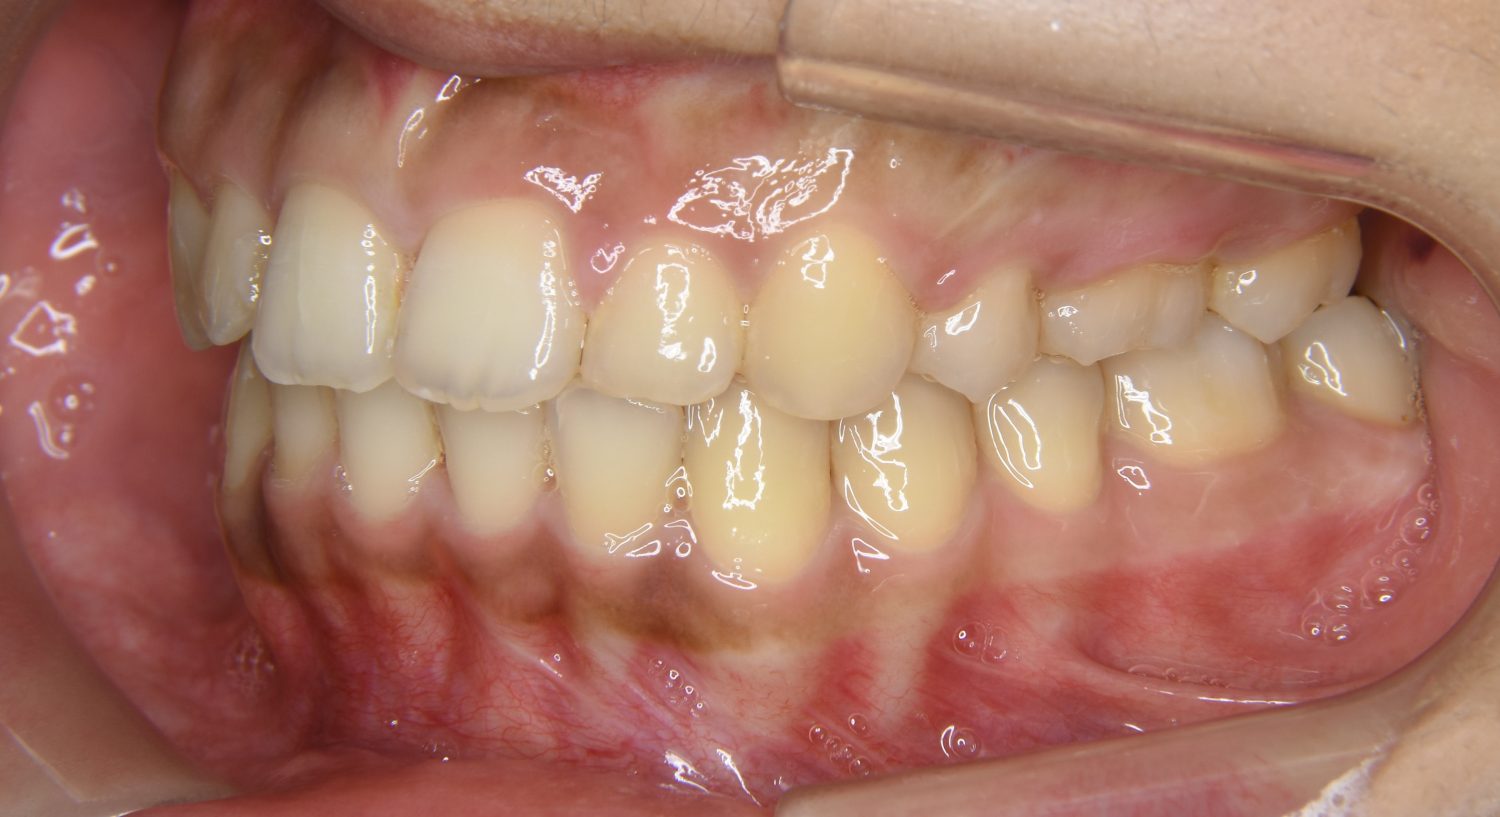

叢生の症例紹介②

Before

After

主訴

歯の凸凹を治したい。

治療内容

アライナー(インビザライン)にて非抜歯で治療を行いました。

治療費

1,150,000 円(税込)

治療期間

26ヶ月

通院回数

14回

想定されたリスク

※歯根吸収、歯肉退縮、歯髄壊死、顎関節症状

※アライナー(インビザライン)は日本の薬機法未承認の矯正装置であり、医薬品副作用被害救済制度の対象外となる場合があります。

丸山和宏先生

ピーススマイル矯正歯科

上下前歯部に叢生(凸凹)が認められる状態でした。歯列の遠心移動を行うことで機能面および審美面が改善されました。